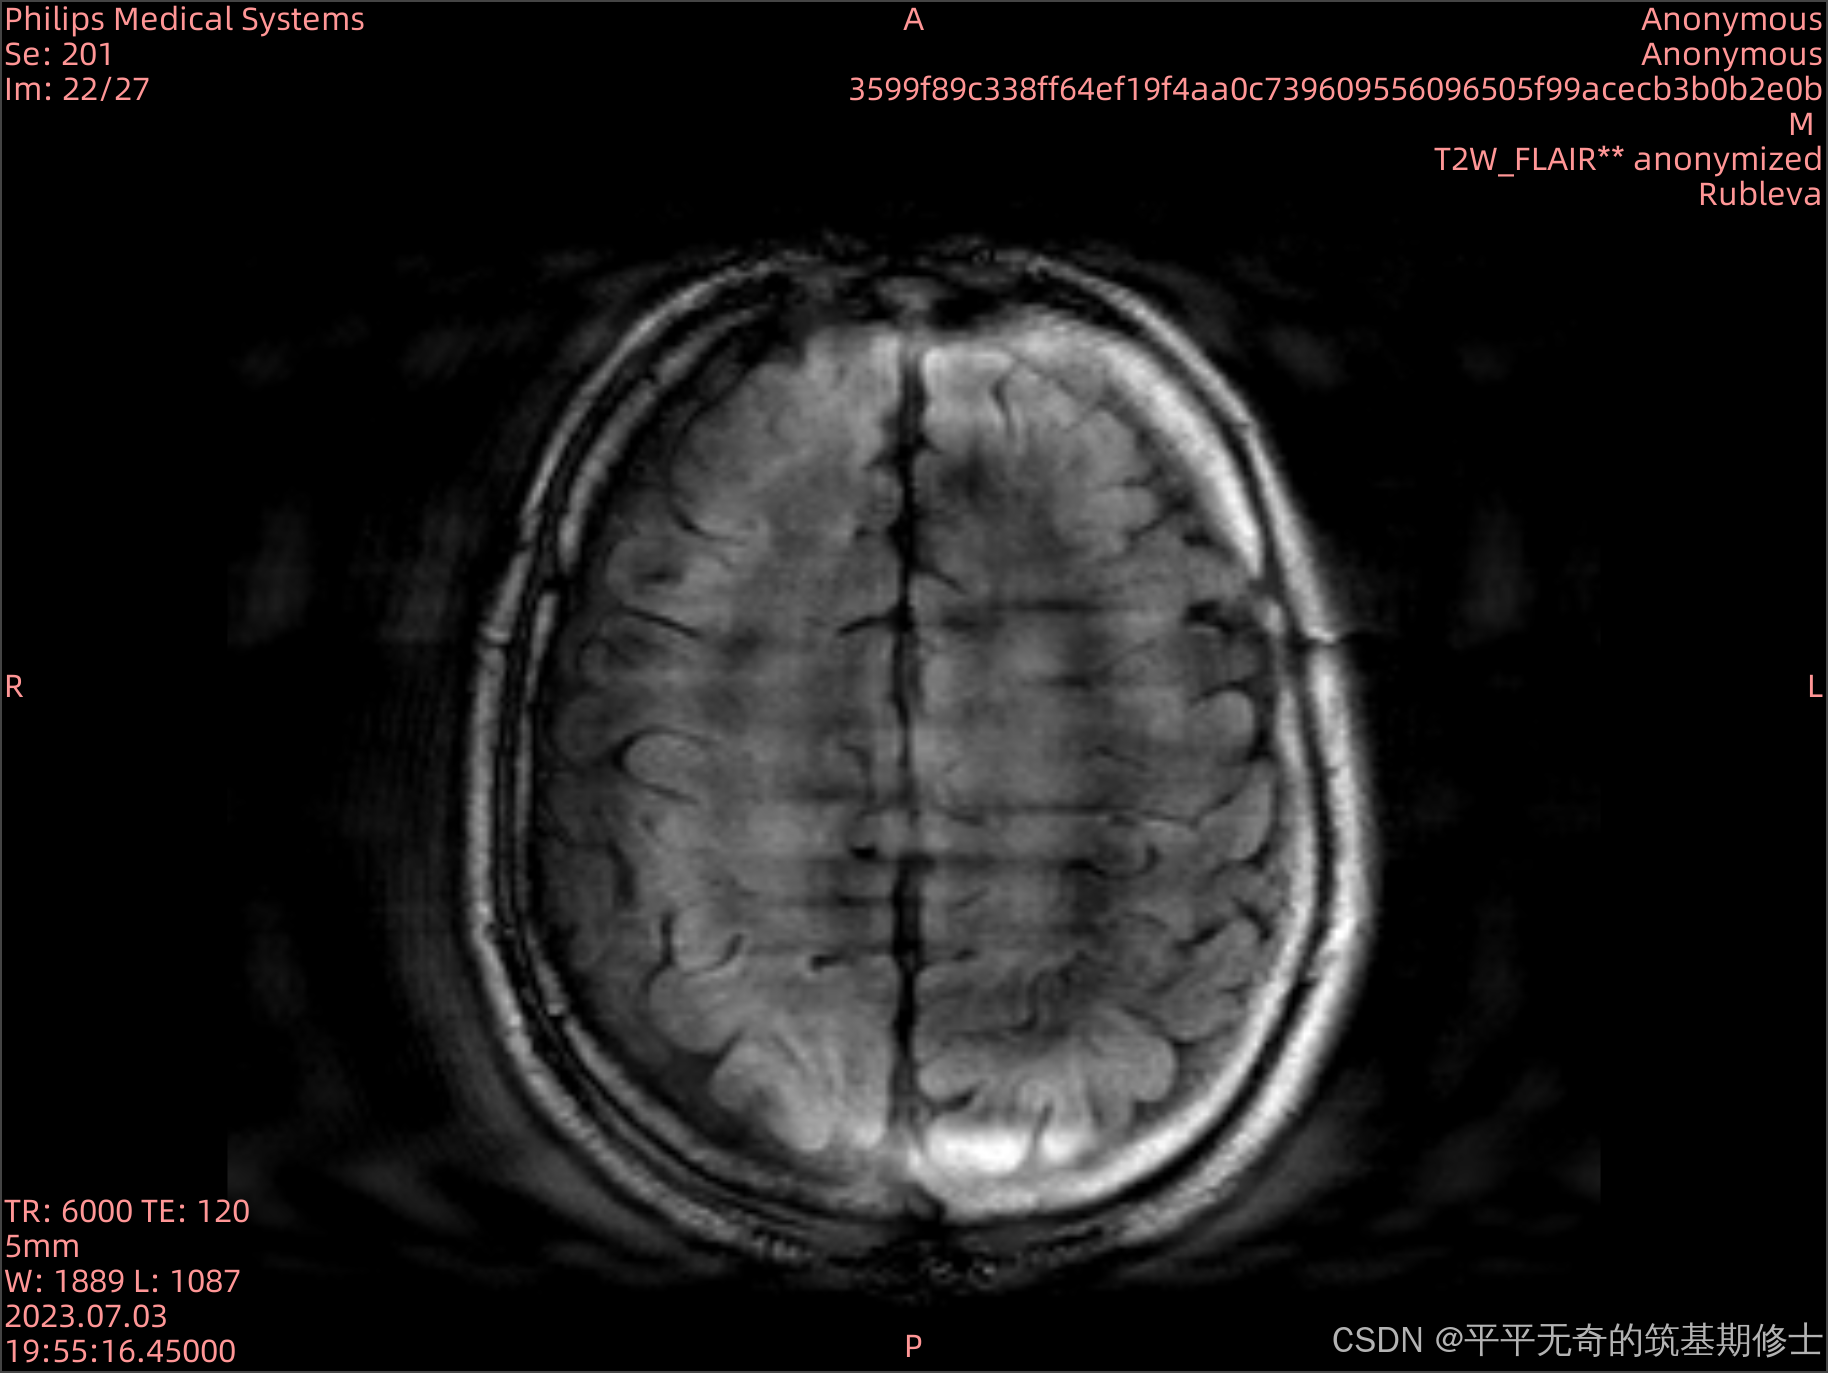

在医学影像中,运动伪影是一种常见的问题,特别是在MRI图像中。这种伪影会影响医生的诊断准确性。为了解决这一挑战,我们开发了一个伪影模拟工具,帮助研究人员分析和减轻伪影的影响。

代码实现了3D MRI图像伪影的模拟,涉及图像频域变换、随机运动轨迹的模拟以及伪影生成的逻辑。是一个医学成像中的运动伪影生成项目。核心功能集中在利用FFT、随机运动模拟和空间变换算法实现图像的随机扰动。

本项目的主要应用领域是医学影像模拟,特别是MRI图像中的运动伪影研究。它适用于:

- 图像分析:研究运动伪影对图像质量和诊断准确性的影响。

- 教育与培训:为医学影像学的教育与研究提供真实的运动伪影数据。

通过load_dicom_as_3d函数,将DICOM格式的切片加载并堆叠为三维数组。此步骤对切片进行排序并提取像素间距信息,确保影像的空间一致性。

- 通过FFT和随机运动轨迹生成伪影,模拟出更接近真实场景的三维MRI影像。